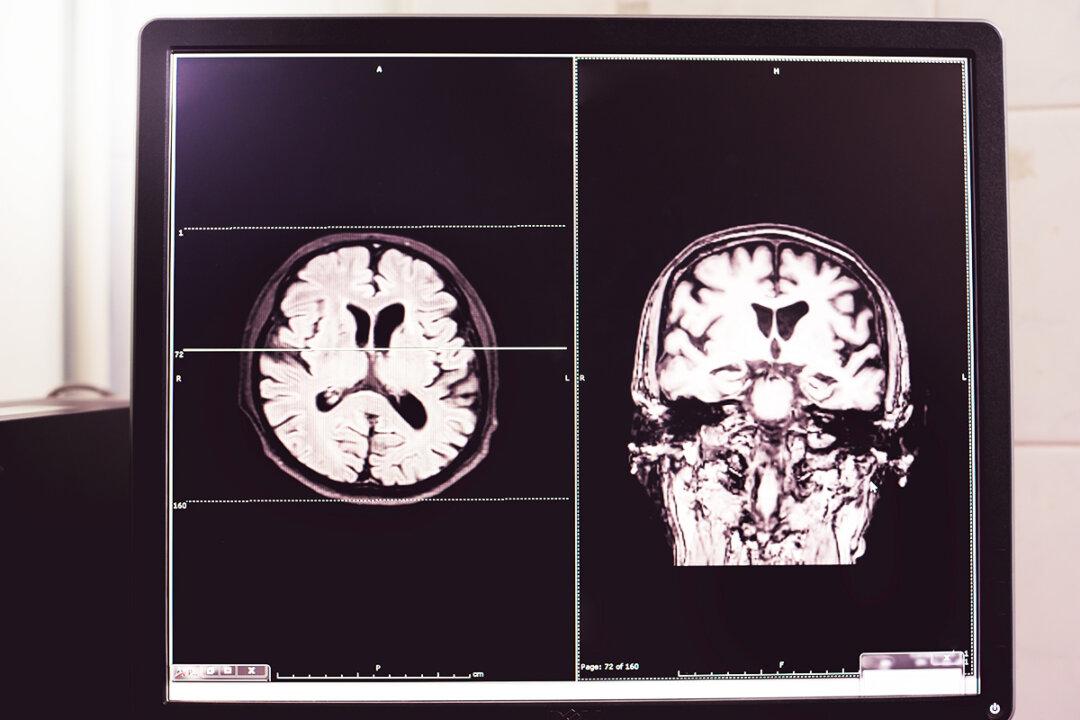

A stroke, also called a brain attack, takes place when the blood supply to a part of the brain gets blocked or when a blood vessel in the brain bursts. In both these situations, parts of the brain can either become damaged or die. A stroke can result in lasting brain damage, long-term disability, and also death. In 2020, stroke was responsible for 6.6 million deaths globally and was the second leading cause of death. An Oct. 9 report from the World Stroke Organization–Lancet Neurology Commission estimates this number to rise by 50 percent to 9.7 million by 2050.